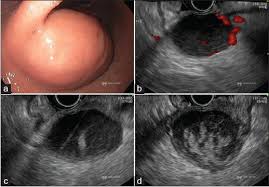

Semasa prosedur, peranti ultrasound kecil dipasang pada hujung endoskop. Endoskop ialah tiub kecil, bercahaya, fleksibel dengan kamera dipasang. Dengan memasukkan endoskop dan kamera ke dalam saluran penghadaman atas atau bawah, doktor dapat memperoleh imej ultrabunyi organ yang berkualiti tinggi.

Oleh kerana EUS boleh mendekati organ yang sedang diperiksa, imej yang diperoleh dengan EUS selalunya lebih tepat dan terperinci daripada imej yang disediakan oleh ultrasound tradisional yang mesti bergerak dari luar badan.

Ultrasound endoskopik ialah prosedur invasif minimum yang menggunakan peranti kamera (endoskop) bersama-sama dengan gelombang bunyi frekuensi tinggi (ultrasound) untuk memeriksa saluran GI dan seterusnya.